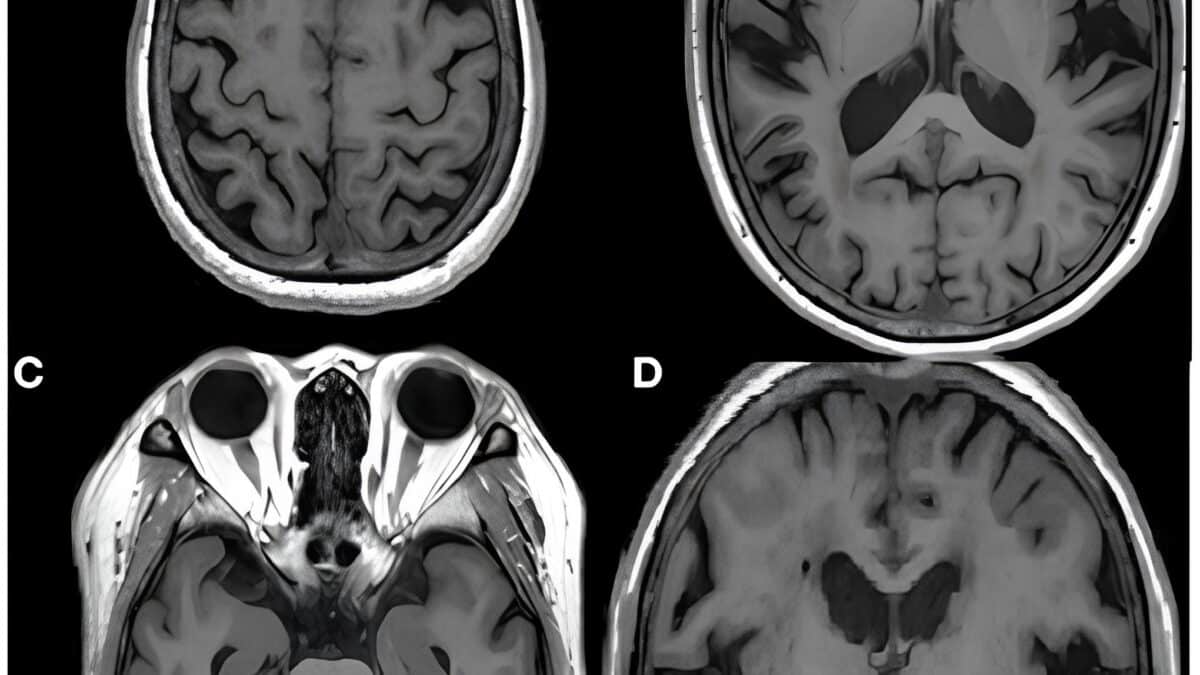

Врачи поставили диагноз: «эротоманический бред», «дистимия» (затяжная, но более мягкая форма депрессии) и «легкое когнитивное расстройство». Эротоманию посчитали вторичной: она была вызвана интернет-мошенничеством на фоне другого психического расстройства. Пациентке назначили антидепрессанты (сертралин) в сочетании с низкими дозами рисперидона, а также поддерживающую индивидуальную и групповую терапию.